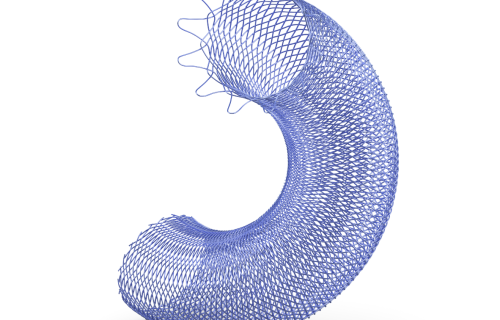

Em Cirurgia Vascular, Endovascular e Radiologia Intervencionista oferecemos uma ampla gama de soluções, incluindo enxertos endovasculares, cateteres de trombectomia e dispositivos de embolização. Esses produtos são vitais para o tratamento de doenças vasculares complexas, como aneurismas e tromboses, proporcionando aos profissionais de saúde as ferramentas necessárias para intervenções precisas e eficazes.

Nossa atuação em Neurorradiologia Intervencionista inclui a oferta de microcateteres e stents especializados para o tratamento de aneurismas cerebrais e outras condições neurológicas críticas. Esses dispositivos são desenvolvidos com tecnologia de ponta para garantir a máxima segurança e eficácia durante os procedimentos, ajudando a preservar a integridade cerebral dos pacientes.